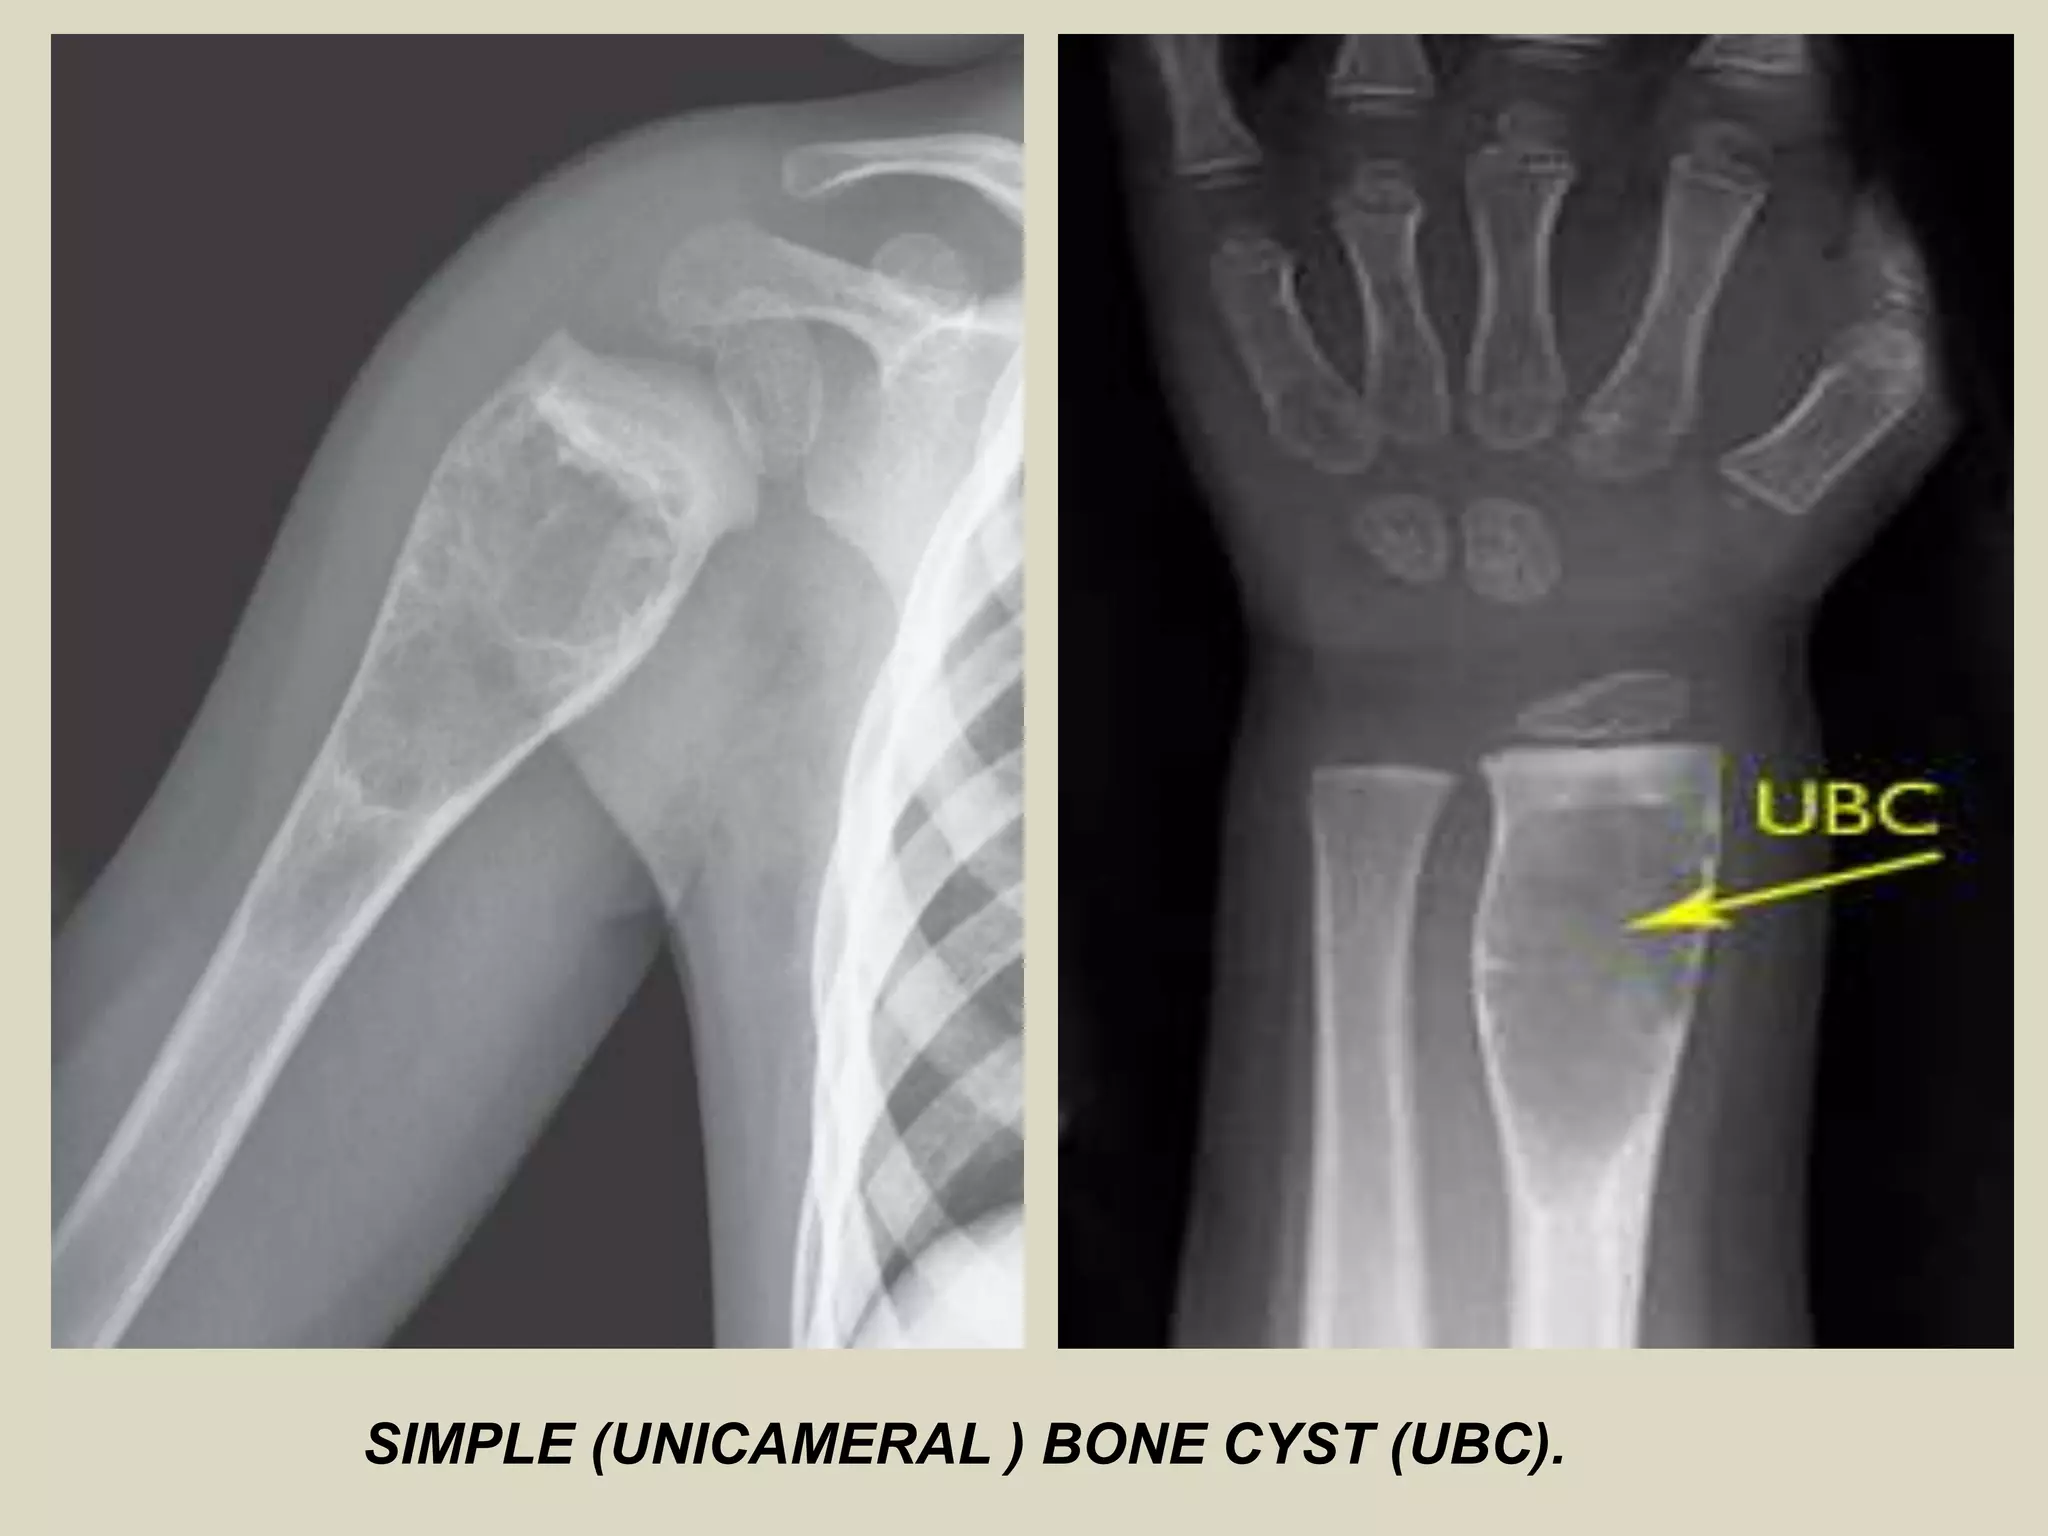

SIMPLE (UNICAMERAL ) BONE CYST (UBC)

Definition:

- Intramedullary, usually unilocular, bone cyst filled with

serous or sero-sanguineous fluid.

Epidemiology:

- 85% of patients in the first decades of life.

- Male: Female ratio 3:1.

Sites of involvement:

- Most common locations:

- proximal humerus

- proximal femur

- proximal tibia

Clinical findings:

- Pain and swelling.

- Patients may present with pathological fracture.

Imaging:

- Well demarcated and radiolucent.

- Typically begins in the metaphysis and extends into the diaphysis.

Gross:

- Fragments of thin whitish membrane

- Usually during surgery you get scant tissue material.

SIMPLE (UNICAMERAL ) BONE CYST (UBC).